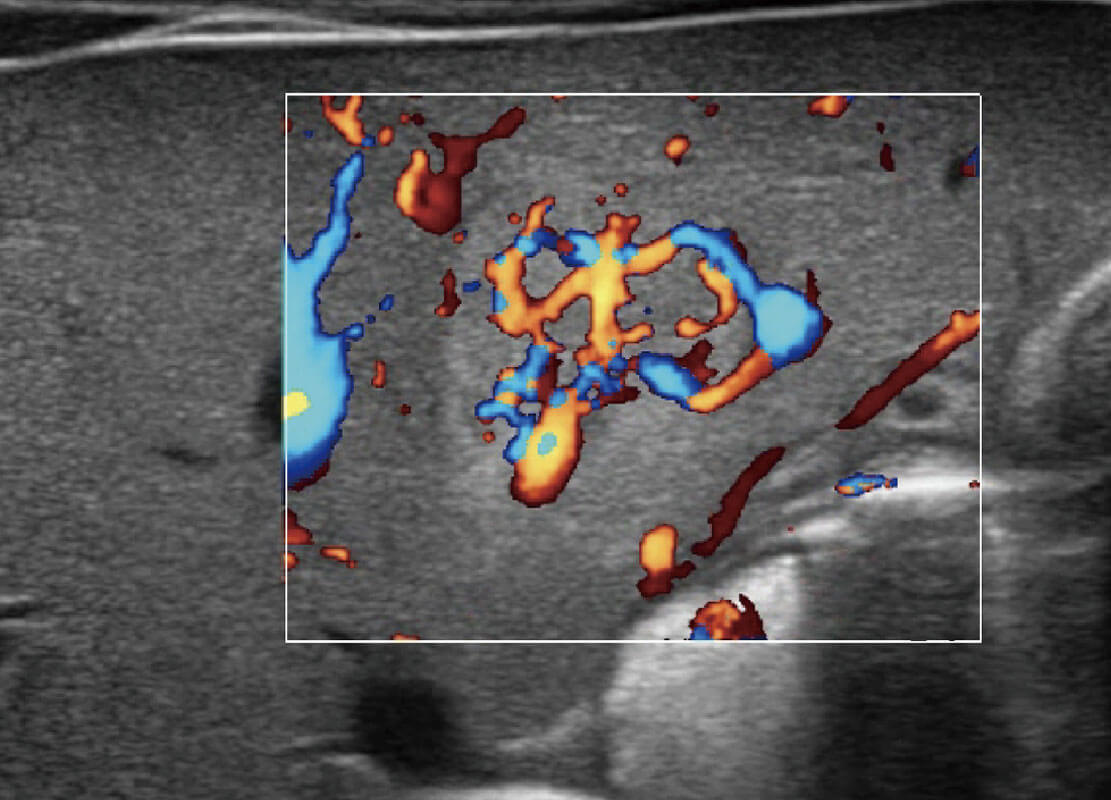

P60优异的图像质量搭载专科探头,在妇科基础疾病的诊断、卵泡生长的监测、输卵管通畅情况的判别等方面为您提供生殖应用方案。

腔内妇科-卵巢

乳腺癌显微血流